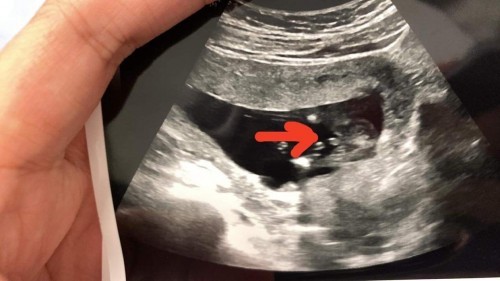

อัลตร้าซาวน์ 14 weeks

ซาวน์ตอน 14 weeks ค่ะ แบบนี้ผู้ชายใช่มั้ยคะแม่ๆ 😂

ผู้ชายค่ะ

ผู้ชาย